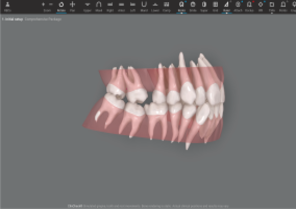

CBCT integration in ClinCheck® Pro software

Auto-generates a 3D model with roots, crown, and bone for more-informed treatment planning.

See patients' roots, crowns, and bone in one auto-generated 3D model with new CBCT integration.

Roots and gingiva

Roots and gingiva